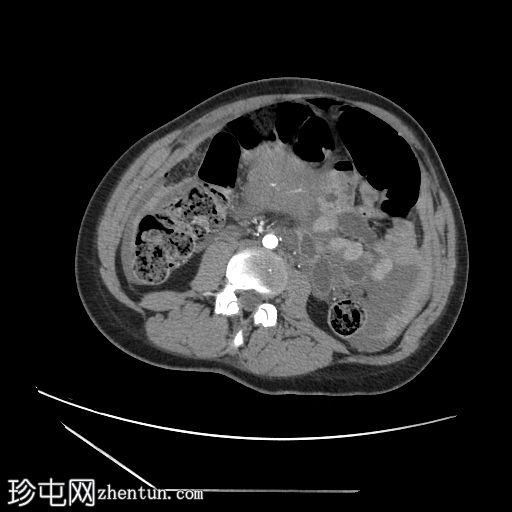

轴位增强扫描

门静脉期

子宫增大,复旧不全,子宫体前壁全层缺损,位于近期剖宫产部位,气体和液体从子宫内膜腔经壁缺损扩散至子宫外旁组织。

膀胱瓣膜血肿和腹壁血肿较大。

腹腔内有大量游离液体和血腹,无活动性出血。

剖宫产术后子宫破裂是一种罕见但严重的并发症。 CT扫描显示子宫前壁全层存在不规则的低密度缺损,而子宫前壁其他部分则呈规则强化。

气体或液体通过子宫壁缺损从子宫内膜腔扩散至腹膜腔或宫旁腔,可提高诊断的特异性。

辅助征象包括腹腔积血、盆腔血肿和腹腔内游离液体。